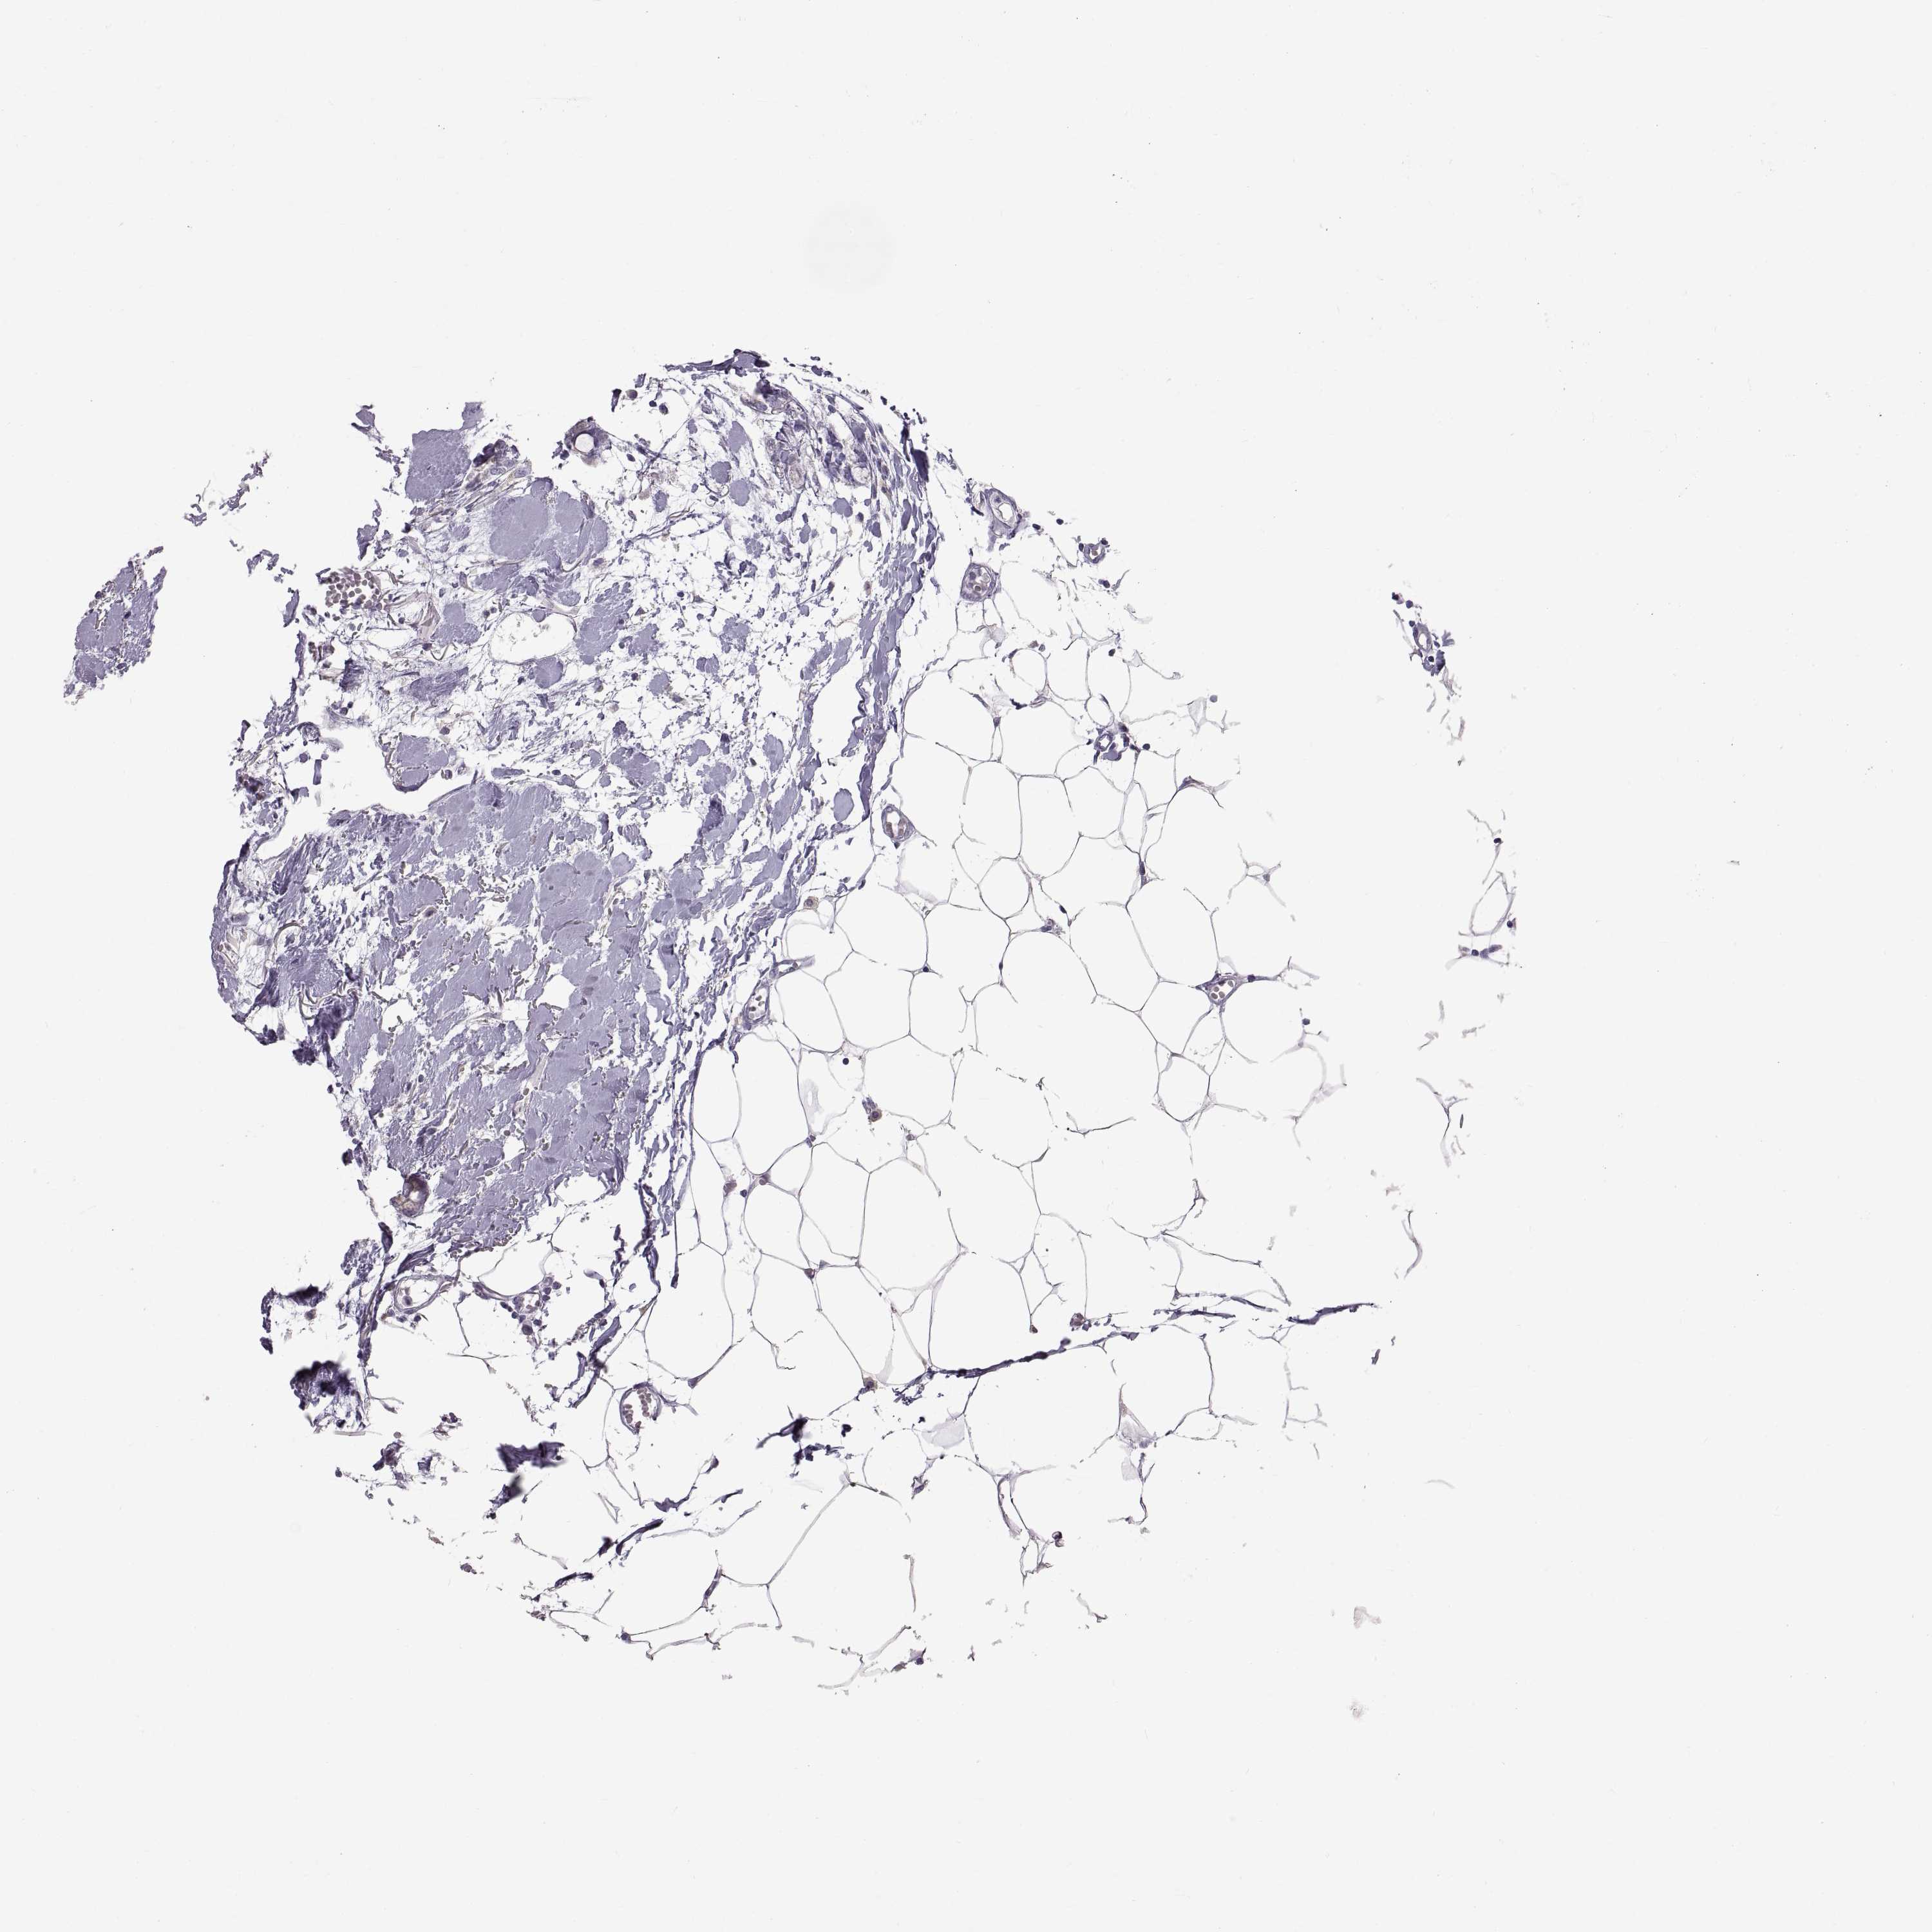

CANCER BREAST CANCER Show tissue menu

BRCA TCGA BRCA VALIDATION PROTEIN EXPRESSION

Breast cancer

Human cancer